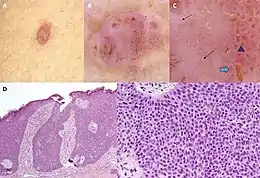

Poromas are rare tumors that in two large review studies represented 0.0058% and 0.134% of all skin tumors; dermal duct tumors are the rarest form of the poromas, representing only 3.3% of these tumors in 3 studies examining 675 poroid neoplasms.[2] They usually occur in the elderly population (mean age 65.1–66.6 in different studies) as small (<2 centimeters), solitary dome-shaped papules, plaques, or nodules, that are skin-colored, pink, red, white, or blue and range from smooth to wart-like, ulcerative,[4] or pyogenic granuloma-like lesions.[10] They may be located on the palms of the hands, soles of the feet, trunk, face, neck, or other cutaneous surfaces[4] such as the areola,[11] nipple,[12] or other areas of the breast,[13] on the scrotum,[14] or on the vulva.[15] Rarely, individuals present with multiple poromas either in one or widespread areas; these cases are termed poromatosis.[3]

Microscopic histopathological examinations of the tumor tissues of all poroma variants stained with hematoxylin and eosin dyes reveal: a) basophilic "poroid cells" (i.e. small, cuboid-shaped cells with oval nuclei which resemble cells in the peripheral layer of the distal portion of eccrine sweat gland ducts[20]) that may form cords and broad columns extending downward from the epidermis; b) larger cuticular cells (i.e. squamous epithelial-like eosinophilic cells that resemble the luminal cells lining eccrine sweat gland ducts[20]); and in some cases c) clear cells (i.e. cells with small nuclei surrounded by pale cytoplasm).[3] Poroma tumor tissues may appear highly vascularized and/or have areas of necrosis, i.e. dead or dying cells. Hidroacanthoma simplex variants are mainly composed of poroid cells, few cuticular cells, and no clear cells and are confined to the epidermis; dermal ductal variants are mostly confined to the superficial dermis and are composed of small solid and cystic nodular aggregates of poroid, cuticular, and clear cells; poroid hidradenoma variants have large aggregates of solid and cystic components and extend deeper into the dermis or even subcutis; and eccrine poroma variants are composed of all three cell types but are primarily located in the epidermis and superficial dermis. Poromas may have 2 or more of these variants in the same tumor tissue and the variants typically have histopathology findings that are not clearly distinguishable from each other.[3]

The great diversity, rarity, and complex terminology of poromas make their diagnosis challenging. They have been misdiagnosed as other types of skin tumors including porocarcinomas, basal cell carcinomas, pyogenic granulomas, skin tags, plantar warts (i.e. warts on the palms or soles), fibromas, hemangiomas, pigmented moles, seborrheic keratosis, trichilemmomas, melanomas, Kaposi sarcomas, and other adnexal tumors. Poromas are typically diagnosed based on their clinical presentation; microscopic histopathology showing tumor tissues consisting of poroid, cuticular, and/or clear cells; and, in unclear cases, the presence of tumor cells that express a YAP1::NUTM1, YAP::MAML2, and/or WWTR1::NUTM1 fusion gene.[3][7] However, these fusion genes also occur in porocarcinomas and cannot be used to differentiate poromas from their malignant counterpart. Poromas and porocarcinomas are distinguished based on their clinical findings and histopathology, e.g. a higher Ki67 labeling index and aberrant expression of p53, RB, and p16 proteins are more frequent in porocarcinoma (see Diagnosis of porcarcinomas).[7] Dermatoscopy, particularly when revealing a "leaf- and flower-like pattern" in a skin tumor, has been used as a strong indicator that the lesion is a poroma, but confirmation of this diagnosis ultimately relies on histopathological analyses.[3]